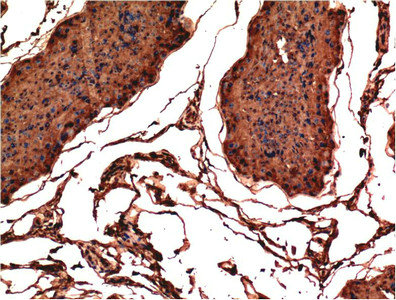

• Immunohistochemical analysis of paraffin-embedded Rat Testis Tissue using CSB-MA484077 at dilution of 1:200.